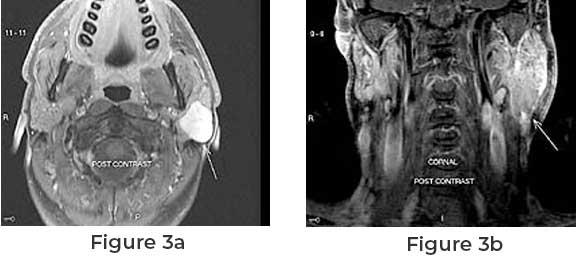

- MRI and CT Scans: Essential for visualizing

the tumor's size, location, and its relationship with surrounding structures.